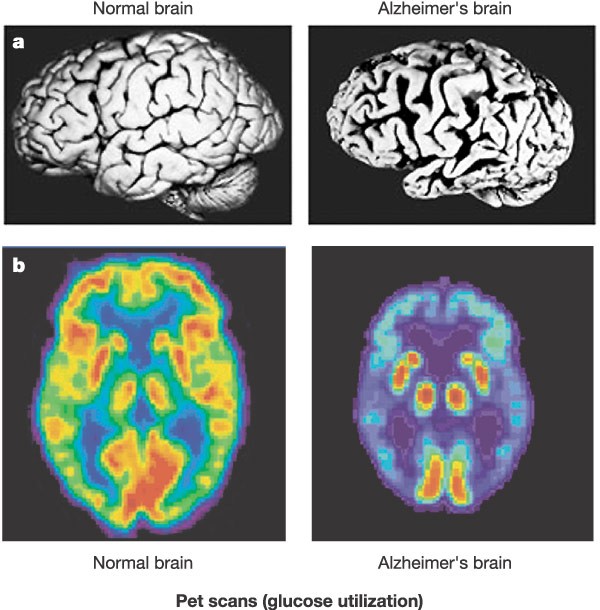

"Artificial Intelligence Assisted Alzheimer's Disease Prevention and Recommendations (AAADPR)” is an artificial intelligence enabled web-based application. The application analyzes sleep pattern, and MRI/PET scans to recommend the personalized best possible solutions, services, and nutritional products for overall health and wellbeing. AAADPR aims to give their users early indications of cognitive problems and their solutions.